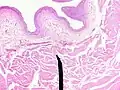

When viewed under a microscope, the bladder can be seen to have an inner lining (called epithelium), three layers of muscle fibres, and an outer adventitia.[8]

The inner wall of the bladder is called urothelium, a type of transitional epithelium formed by three to six layers of cells; the cells may become more cuboidal or flatter depending on whether the bladder is empty or full.[8] Additionally, these are lined with a mucous membrane consisting of a surface glycocalyx that protects the cells beneath it from urine.[14] The epithelium lies on a thin basement membrane, and a lamina propria.[8] The mucosal lining also offers a urothelial barrier against the passing of infections.[15]

These layers are surrounded by three layers of muscle fibres arranged as an inner layer of fibres orientated longitudinally, a middle layer of circular fibres, and an outermost layer of longitudinal fibres; these form the detrusor muscle, which can be seen with the naked eye.[8]

The outside of the bladder is protected by a serous membrane called adventitia.[8][16]

Vertical section of bladder wall -

Layers of the bladder wall and cross-section of the detrusor muscle

Anatomy of the male bladder, showing transitional epithelium and part of the wall in a histological cut-out